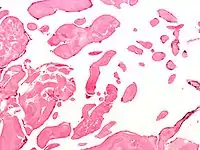

| Low magnification micrograph of an excised aortic valve papillary fibroelastoma showing the characteristic avascular branching papillae, H&E stain | |

Papillary fibroelastoma are typically found and accurately diagnosed by imaging. The diagnosis is confirmed by pathology. Histologically, papillary fibroelastomas have branching avascular papillae, composed of collagen, that are covered by endothelium.